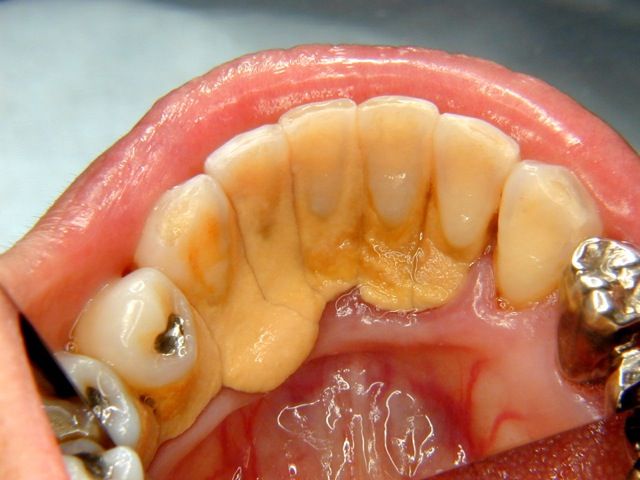

23歳でこれはいけませんか?

4無念Nameとしあき26/03/23(月)11:57:02No.1395803647そうだねx27

>23歳でこれはいけませんか?

問題ないと思えるなら歯じゃなくて脳に障害あると思う

>23歳でこれ

明らかに拾ってきた画像だけど

23歳ってのはどこから?